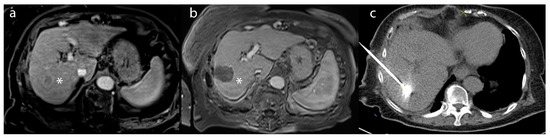

Figure 3. A 62-year-old female patient with (a) an arterially-enhancing lesion (*) in segment 8, compatible with hepatocellular carcinoma on post-contrast T1-weighted imaging. (b) After TACE, the lesion (*) demonstrated a lack of enhancement, compatible with a complete radiographic response on the 2 month follow-up CT. (c) Intraprocedural angiogram of TACE depicting the embolic distribution of the right lobar artery.

The conventional transarterial chemoembolization (cTACE) procedure functions through a distinctive mechanism of action that involves impeding tumor-feeding arteries by injecting chemotherapeutic agents, namely doxorubicin or cisplatin, mixed with the radiopaque contrast agent, lipiodol (Figure 3) [3,42,44,45,46]. The process is intended to limit the supply of nutrients and oxygen to the tumor, thereby causing its necrosis and subsequent shrinkage [46]. This embolic technique works by creating an embolus within the tumor-feeding artery, obstructing the blood flow, and trapping the chemotherapeutic agents within the tumor, leading to a local, sustained release of the chemotherapeutic agents (Figure 3c) [46]. The lipiodol facilitates the visualization of the infused agents under fluoroscopy and CT imaging, thus aiding in the accurate delivery of the embolic agent to the targeted area. The procedure itself takes approximately 1–2 h, and patients are typically monitored overnight before being discharged the following day. Incorporating drug-eluting beads, designated as DEB-TACE, has become increasingly popular in numerous medical centers, as it employs embolic microspheres or beads containing chemotherapy drugs [47]. Among the benefits of DEB-TACE over conventional TACE, it enables a steady and regulated administration of the therapeutic agent, thereby prolonging local exposure to the tumor while minimizing systemic exposure [48,49,50].